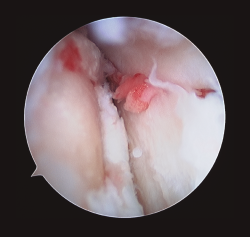

La artroscopia en los pacientes con fractura de tobillo ofrece la ventaja de valorar la reducción conseguida, el tratamiento de las lesiones del cartílago, valorar el daño ligamentoso, la extracción de cuerpos libres, la liberación de tejidos de ambos desfiladeros y la valoración de la sindesmosis(7,8,9)(Figura 5).

Figura 5. Valoración de la reducción articular de lesiones añadidas.